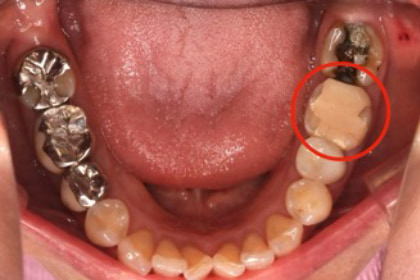

近所のかかりつけの歯科医院で、「再治療できないから奥歯を抜くしかない」と言われた。

あきらめきれず、HPで探して当院へ来院。

外すと中がドロドロに虫歯に感染していました。

折れて残っていた機具を除去